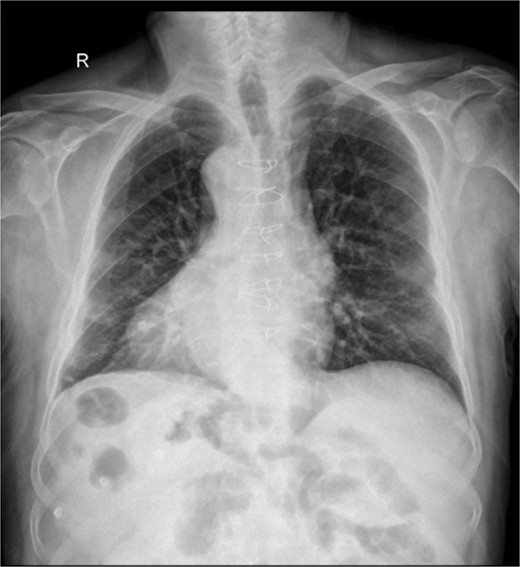

A chest X-ray showed dextrocardia as seen in Fig. 1.